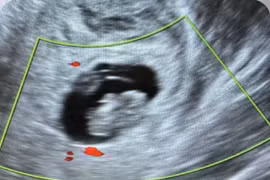

Siêu âm không phát hiện túi thai, thai phụ vỡ khối chửa nguy kịch

Đối với phụ nữ trong độ tuổi sinh đẻ, khi có rối loạn kinh nguyệt, thử thai cho kết quả dương tính, cần chủ động thăm khám và theo dõi sớm.